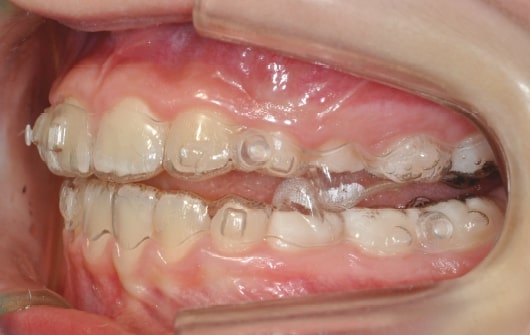

Malocclusion A6 Correction of Mandibular Retrusion in Growth phase patient | Skeletal Class II | Class II Division 1 malocclusion | Deep bite | Mixed dentition

Initial Photos and datas

Clinical examination and diagnosis

DENTAL:

• Molar and Canine class 2 on the right side – Molar and Canine clss 1 on the left side

• Upper diastema (11-21)

• Increased Overjet

• DeepBite

• Reduced Transversal Diameters

• Deviated Lower Midline 2 mm to the Right